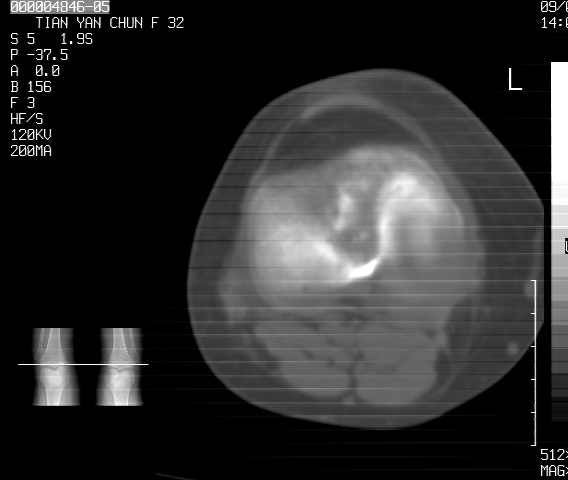

标题: CT18487:请会诊,女32岁,左膝疼痛数日 [打印本页]

标题: CT18487:请会诊,女32岁,左膝疼痛数日

关节面软骨有硬化环考虑退行性变

定位片可见髁间棘骨质增生,支持膝关节退行性变。

定位片可见髁间棘骨质增生,支持膝关节退行性变。建议mri 检查

考虑骨性关节炎